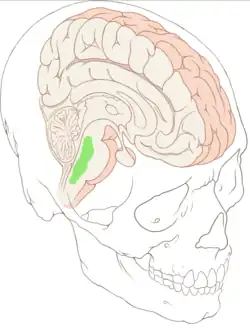

Núcleos da rafe

Os núcleos da rafe são núcleos encontrados no tronco cerebral. Sua principal função é a secreção de serotonina para o resto do cérebro.[1]

Há diversos núcleos da rafe:[2]